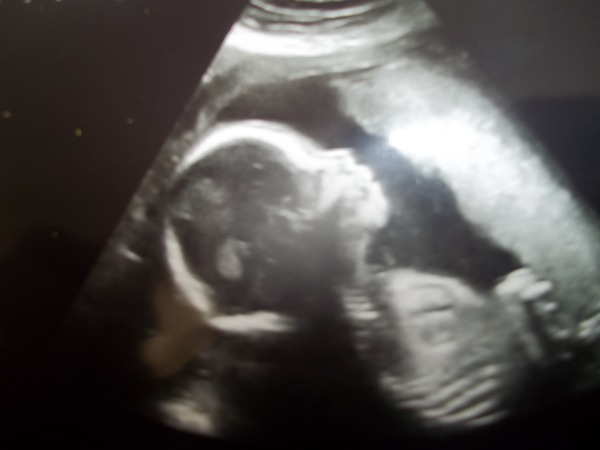

Anyway, I had the scan. Placenta is high (yay!) and it's a little baby girl! Here she is, all pretty like :)

yay for a girl rhi :) cute scan pic there

Beautiful scan pic rhi